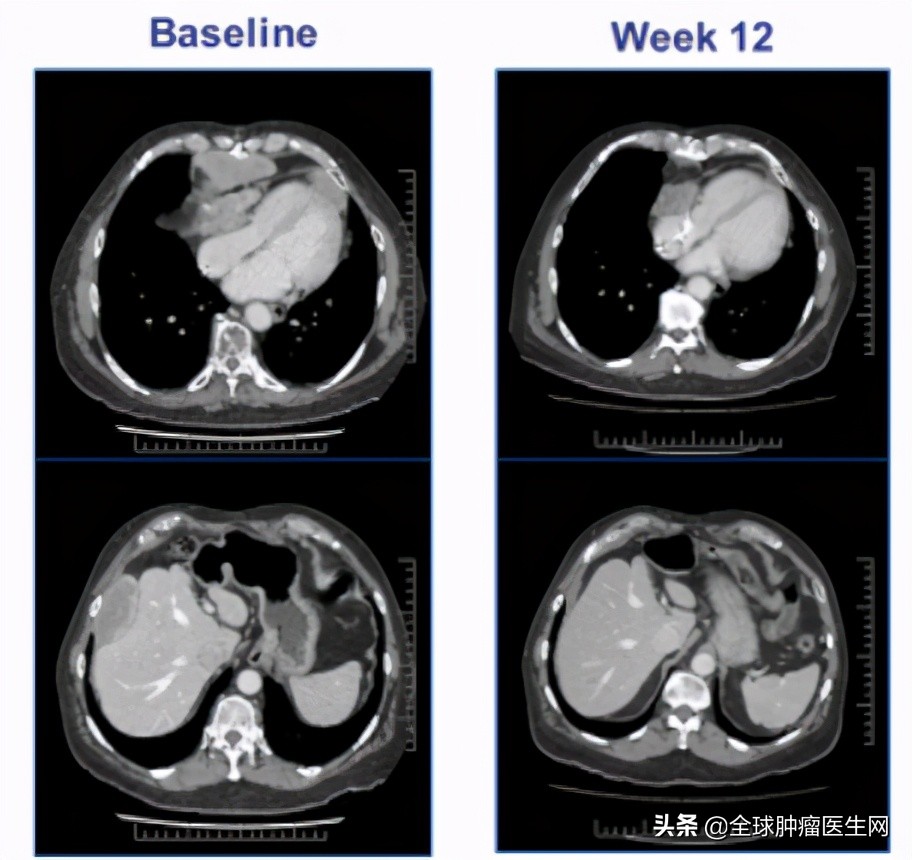

会议上报道了一位67岁的男性晚期滑膜肉瘤患者,MAGE-A4高表达(100% 3),接受9.95*10^9ADP-A2M4 T细胞治疗12周后,最大的肿瘤病灶(155mm)缩小了45%,随着进一步的治疗,肿瘤缩小了71%。